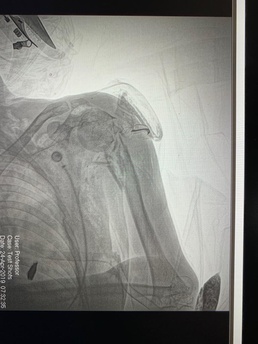

Chest X-Ray

Spc. John Stauffer

25 September 2019

Howard gave a real-world example of a patient with a gunshot wound and collapsed lung, during her deployment.

“We didn’t know where the bullet had gone,” she said. If it had gone deeper into the body, the patient would have needed an evacuation to an operation room at a location…. There was simply no way to find out without the other team’s x-ray machine. “It turns out it was stuck on the left side of his chest,” said Howard.

Which was good news. The bullet had not gone further into the body and the patient did not need a helicopter evacuation, keeping the helicopter available for a more critical situation.